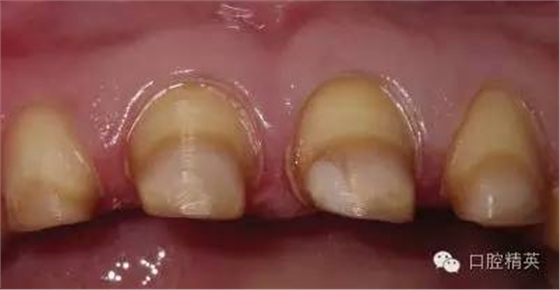

關(guān)于基礎(chǔ)治療。牙周治療和根管治療是美觀修復(fù)的基礎(chǔ)。根據(jù)術(shù)前檢查,常規(guī)先行全口潔治,必要時(shí)局部深層次的牙周治療,待牙周情況穩(wěn)定后,再考慮牙體預(yù)備與取模(見(jiàn)圖1、2)。在牙周炎未控制或牙齦紅腫的情況下,是不可能預(yù)備好牙齒,不可能取得清晰的印模,更談不上成功的美觀修復(fù)。

牙體預(yù)備中支點(diǎn)一定要穩(wěn),手法輕柔,切忌傷及牙齦及鄰牙。由于LAVA冠有著較高的強(qiáng)度,所以牙體預(yù)備較傳統(tǒng)烤瓷冠或其它全瓷冠要少些,最薄可以備0.7mm,最大限度的保留了天然牙體。理想的預(yù)備應(yīng)包括360毅肩臺(tái)或水平角不小于5毅的淺凹型肩臺(tái),垂直預(yù)備角度至少有4毅,肩臺(tái)預(yù)備內(nèi)側(cè)角和咬合面線角一定要圓滑。當(dāng)然在這一過(guò)程中,助手與患者的配合也非常重要,在給醫(yī)生提供一個(gè)清晰舒適的視野的同時(shí),讓患者也要感到舒適,保證牙備的順利進(jìn)行,形成完美的預(yù)備體。牙體預(yù)備示例見(jiàn)圖8。